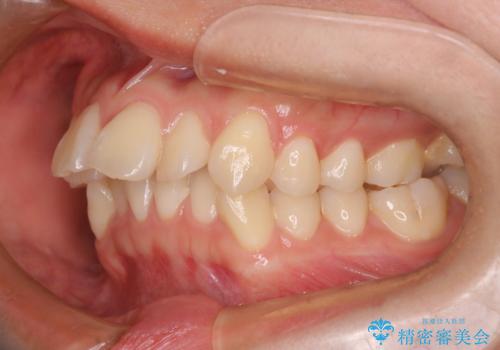

- 口元が出てるのが気になるとのことで来院されました。

上下左右前から4番目の歯を抜歯して前歯を後方に下げて、口元を下げる計画としました。

口元を大きく改善したい場合は抜歯が必要となることが多いです。